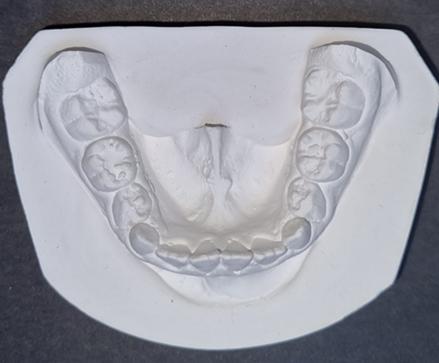

1. Carpio-Deheza G. Manual de instrucciones para la presentación de protocolos y monografías de diplomados, protocolos y tesis de espcialidad clínica/ quirúrgica, tesis de maestrías y doctorados en salud. Cochabamba: Universidad Mayor de San Simon, Facultad de Medicina Dr. Aurelio Melean, post grado UMSS; 2019.

2. Patrias K. Citing Medicine; The NLM Style Guide for Authors, Editors, and Publishers. [Online].: Bethesda (MD): National Library of Medicine (US); 2007 [cited 2022 marzo 29. Available from: https://www.ncbi.nlm.nih.gov/books/NBK7256/.